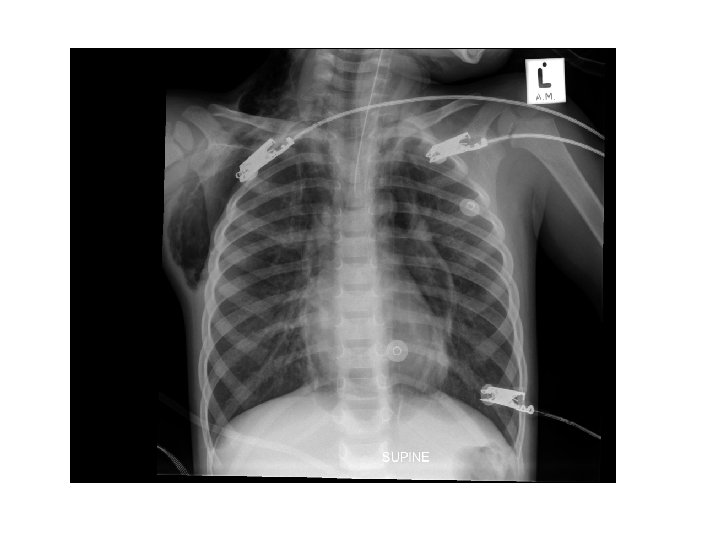

Chest X-ray in severe asthma • Relevant in search for underlining complications – Pneumonia – Air leakages – Collapse • Ventilated patients

Asthma complications • • • • Pneumothorax Pneumomediastinum Pneumopericardium Pulmonary interstitial emphysema Pneumoretroperitoneum Cardiac arrhythmias Myocardial ischaemia or infarction Mucus plugging Atelectasis Pneumonia Electrolyte disturbances – Hypokalaemia – Hypomagnesaemia – hypophosphataemia) Lactic acidosis Hyperglycaemia Theophylline toxicity

Ventilation • Positive pressure ventilation is complicated by severe airway obstruction and air trapping, which results in hyperinflated lungs that may resist further inflation and has a high risk of barotrauma. • Asthma is a disease increased airway resistance, resulting in prolongation of the time constant (the time needed for lung units to fill and empty). Slow ventilator rates are needed. • In the face of high peak airway pressures, the principle of mechanical ventilation of status asthmaticus is controlled hypoventilation, tolerating higher levels of PCO 2 in order to minimize tidal volume and peak inspiratory pressures. • Permissive hypercapnia can be tolerated as long as the patient remains adequately oxygenated. • A longer I: E ratio, often greater than 1: 3 -4, helps allow time for optimal exhalation, facilitating ventilation and avoiding excessive further air-trapping (auto-PEEP).